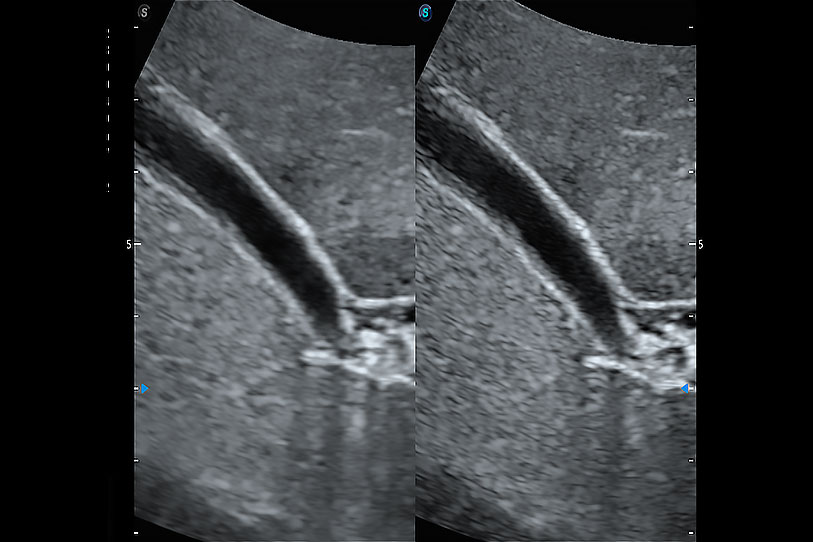

ProPet 70 进一步提升了微米成像算法,更加注重对基础原始图像的还原和保留,在有效减少斑点噪声、增强组织边界显示的同时,避免过度优化丟失真实的解剖信息。